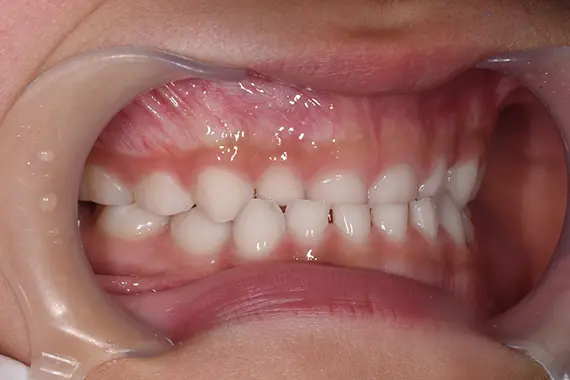

【症例4】8歳男児の症例

受け口の処置を早めに対処していきたいとの相談でご来院頂きました。

矯正前:横から